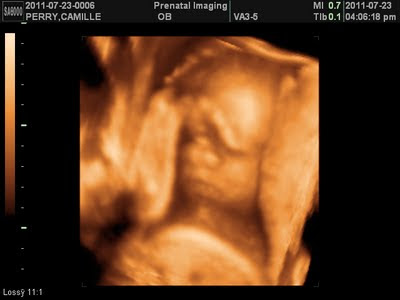

I went in for another 3D/4D ultrasound this week. This time at a different facility. My darn placenta was in the way of seeing all of Max's face. If it's not his hands, its something else! Go figure. The first picture shows Max during our first session. Thank God we came back for a second session (no charge to us), because the pictures came out amazing. My placenta was still blocking part of his face but you can definitely see his cute nose and chubby cheeks! What a cutie pie!

August 13th

August 17th

This past weekend we had a 3D/4D ultrasound. We are happy to report that we're still having a boy! LOL! Unfortunatley, the images are blurry and Max was unwilling to show his face. We will be going in for another session in a few weeks. Hopefully, he will cooporate then!